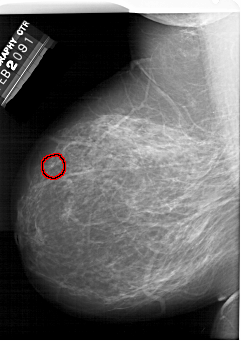

FILE: A_1407_1.LEFT_CC.OVERLAY

TOTAL_ABNORMALITIES 1

ABNORMALITY 1

LESION_TYPE CALCIFICATION TYPE PLEOMORPHIC DISTRIBUTION CLUSTERED

ASSESSMENT 4

SUBTLETY 3

PATHOLOGY BENIGN

TOTAL_OUTLINES 1

LEFT_CC LINES 6811 PIXELS_PER_LINE 4501 BITS_PER_PIXEL 12 RESOLUTION 43.5 OVERLAY